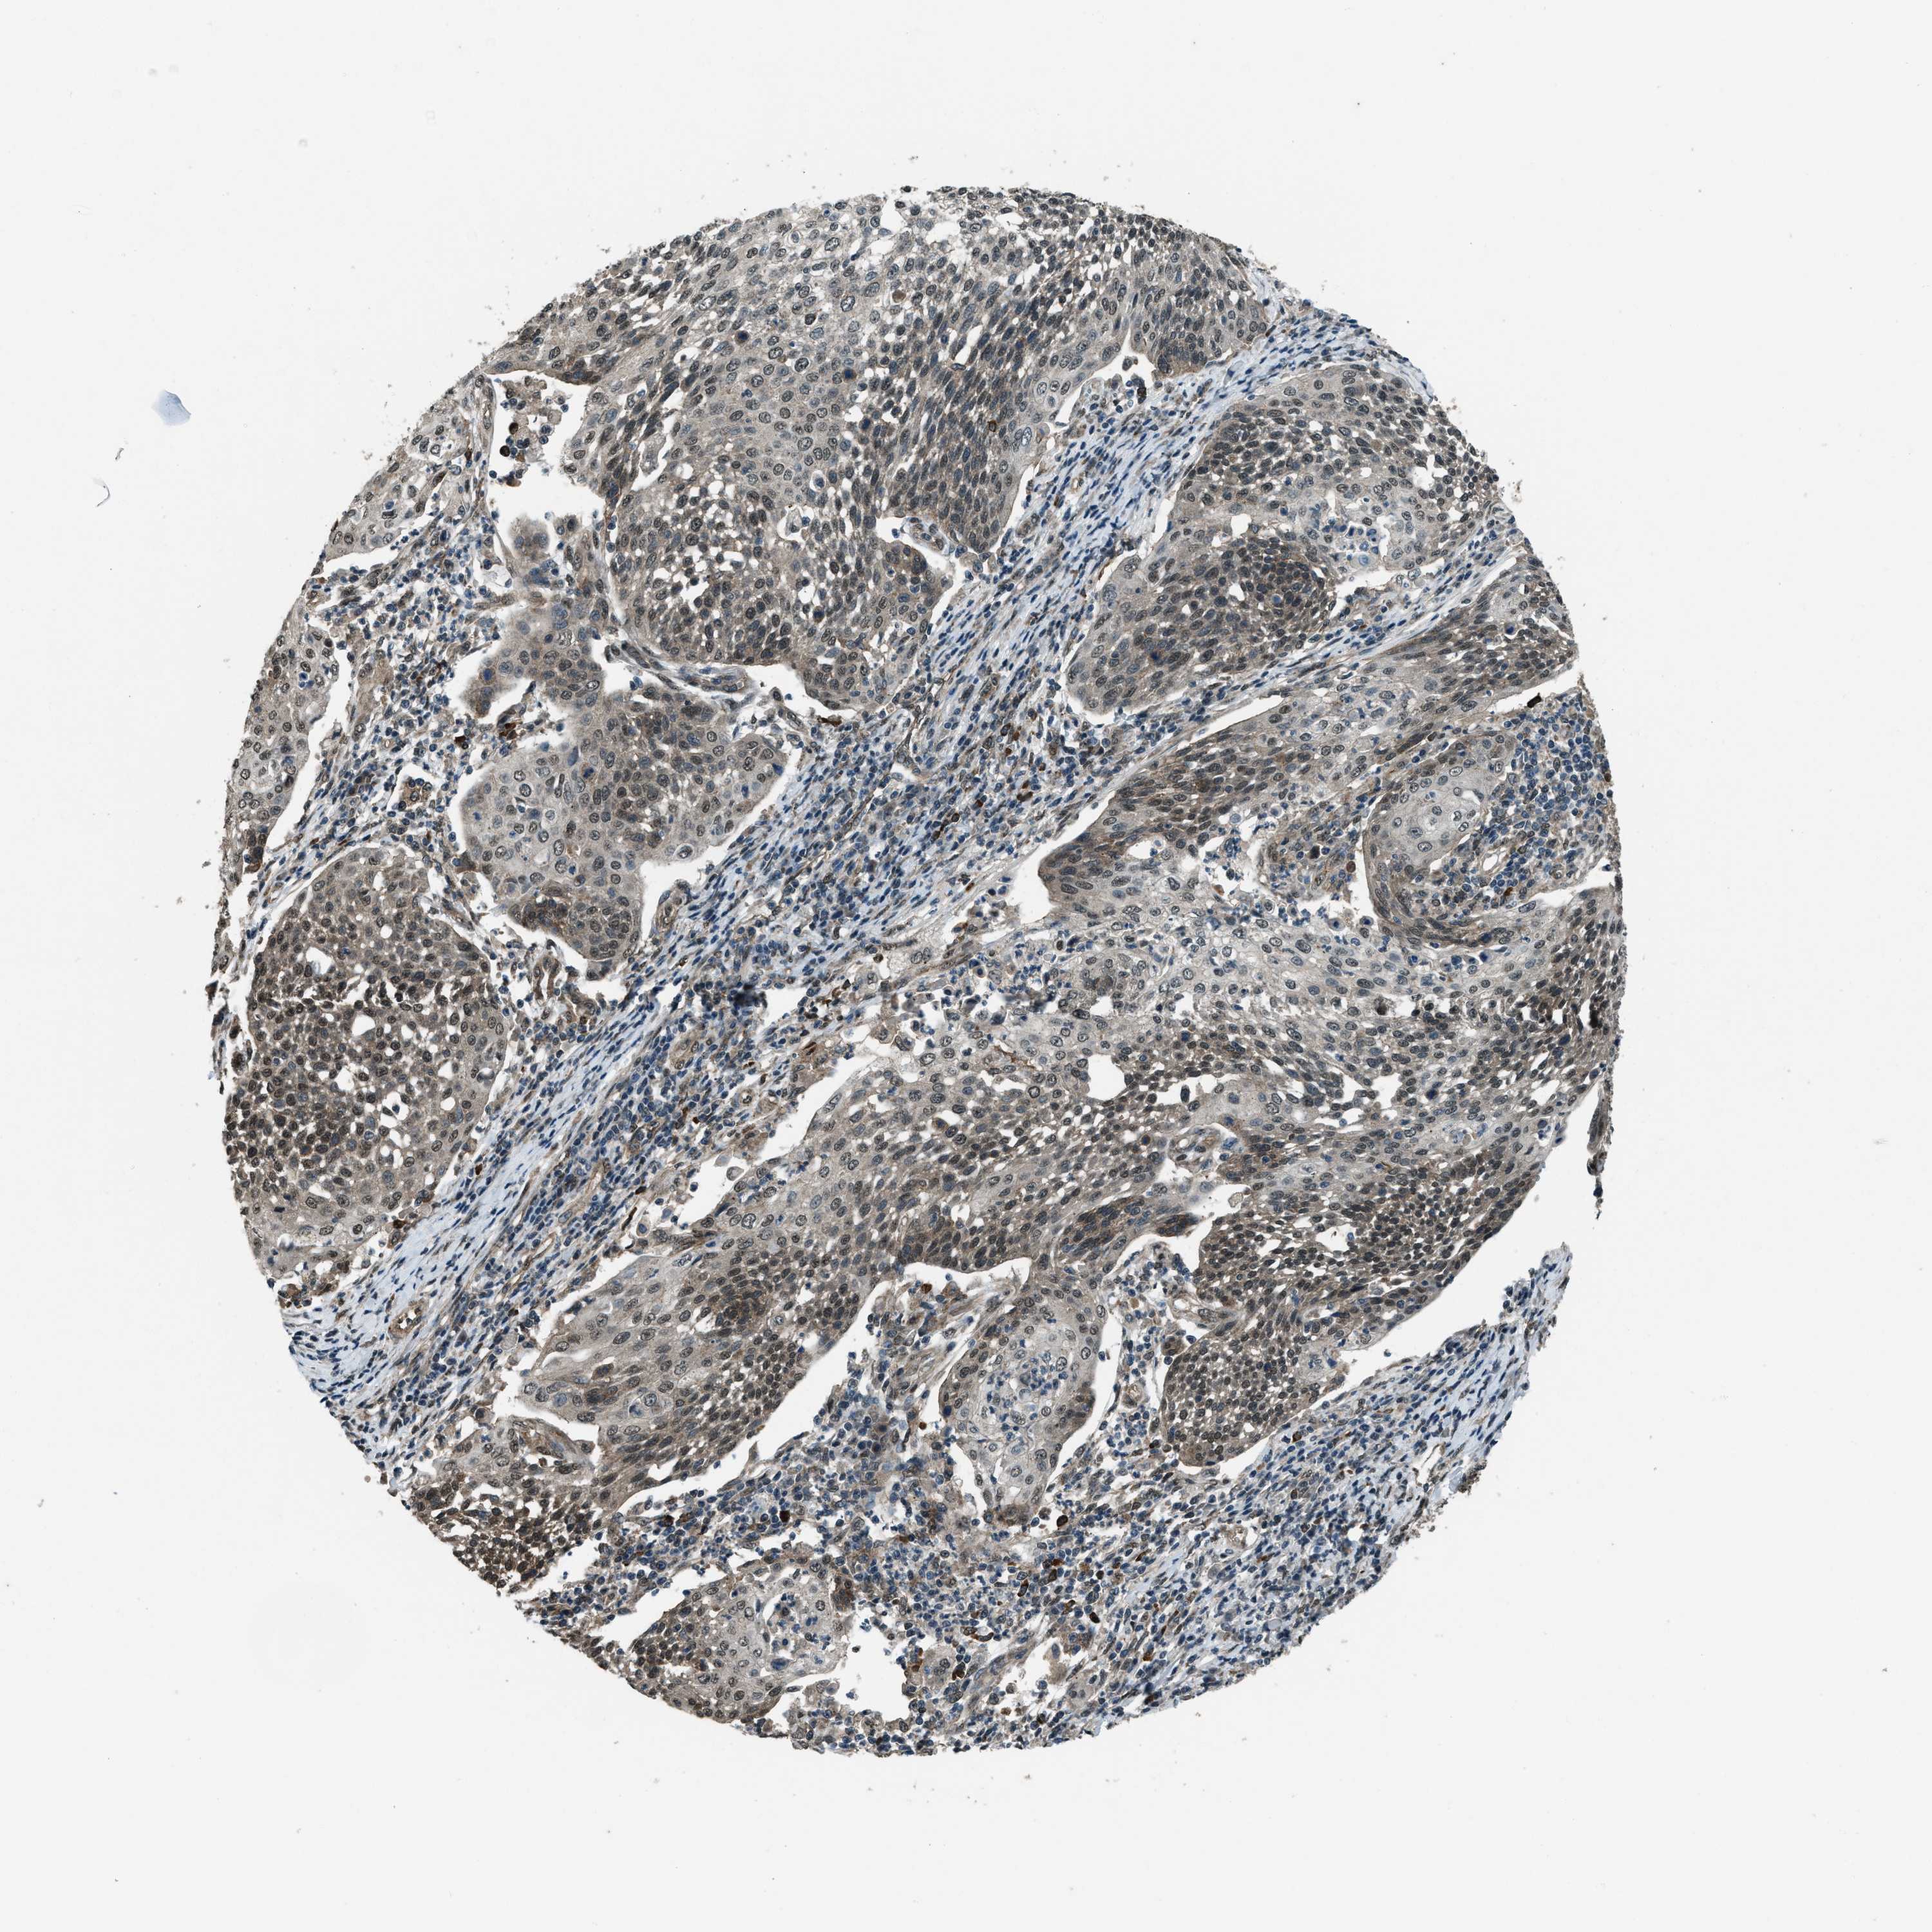

CERVICAL CANCER - Protein expressioni

A mouse-over function shows sample information and annotation data. Click on an image to view it in a full screen mode. Samples can be filtered based on level of antibody staining by selecting one or several of the following categories: high, medium, low and not detected. The assay and annotation is described here.

Note that samples used for immunohistochemistry by the Human Protein Atlas do not correspond to samples in the TCGA dataset.

Antibody stainingi

Antibody staining in the annotated cell types in the current human tissue is reported as not detected, low, medium, or high, based on conventional immunohistochemistry profiling in selected tissues. This score is based on the combination of the staining intensity and fraction of stained cells.

Each image is clickable and will lead to virtual microscopy that enables deeper exploration of all samples and also displays staining intensity scores, fraction scores and subcellular localization as well as patient and tissue information for each sample.

Antibody HPA020095

Antibody HPA020138

Antibody CAB010878

Antibody CAB080402

Squamous cell carcinoma, NOS